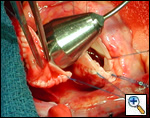

Ensure similar orifice sizes between the proximal and distal ascending aorta after patch augmentation by the use of a sizing dilator.

Transesophageal echocardiography to assess completeness of repair, coronary blood flow postoperatively, wall motion abnormalities, and adequacy of aortic valve.